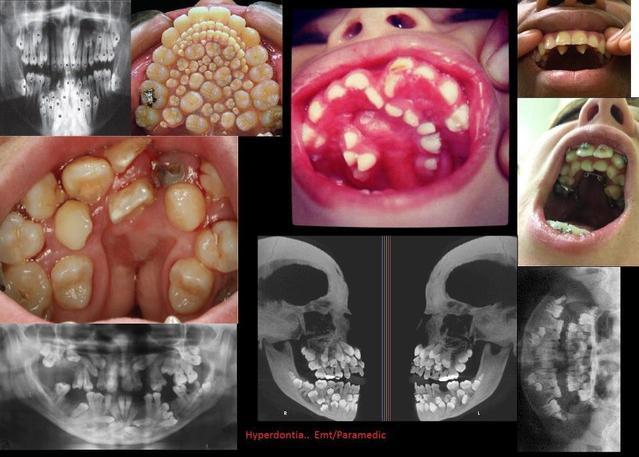

Hyperdontia.jpg